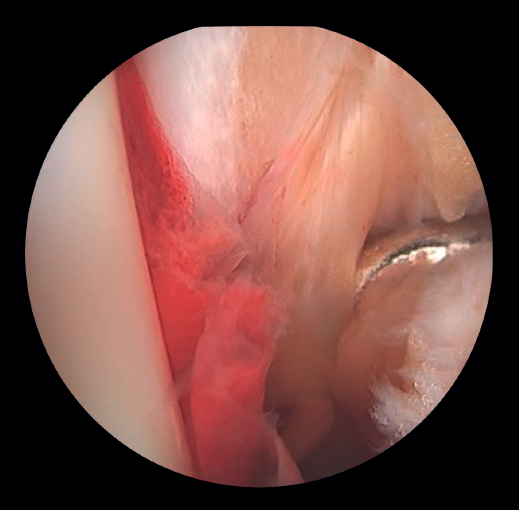

- Assessment of reduction of the posterior malleolus: arthroscopy can be used to verify reduction of the posterior malleolus(5) (Figure 2).

Lee has described a novel technique using a drill guide with ankle arthroscopy for the reduction of joint fragments in posterior malleolus fractures. In particular, this technique is beneficial for patients with trimalleolar fractures who have a depressed joint fragment, as it allows anatomical reduction and minimizes the need for extensive incisions(11). - Extraction of loose bodies. The presence of loose bodies within the joint is a common finding in ankle fractures. One-third of all arthroscopy patients had intra-articular loose bodies removed during surgery (24 out of 71cases)(12). Arthroscopy allows the precise removal of intra-articular loose bodies, which can cause pain, blockage or limitation of mobility, and damage to the joint cartilage(13).